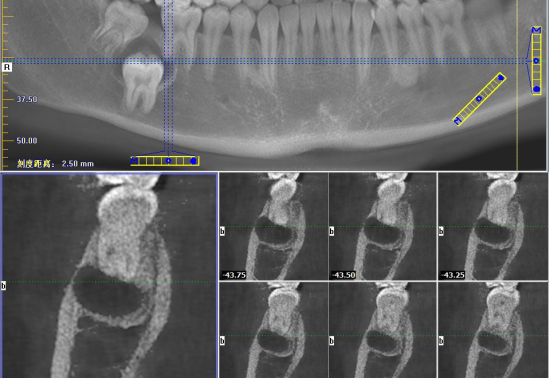

经检查发现,薛同学右下第二恒磨牙(47牙)缺失,右下第三磨牙(48牙)仅部分萌出,牙龈黏膜看起来正常。然而,CBCT检查揭示了真相:右下第二恒磨牙(47牙)竟然“躲藏”在右下第一恒磨牙(46牙)和右下第三恒磨牙(48号牙)的根方,牙冠部还有一个圆形低密度影,形成了含牙囊肿。更严重的是,46牙的远中根已经被吸收,48号牙位置近中,牙根尚未完全形成。

本病例为一青少年男性患者,以右侧下颌磨牙阻生、缺失为主诉。影像学检查明确47牙为埋伏阻生伴含牙囊肿,且已导致邻牙46牙牙根吸收,48牙也存在阻生情况。该情况符合口腔颌面外科手术干预指征,需行手术治疗以摘除囊肿、拔除阻生牙,防止病变进一步发展并保护邻牙健康。面对这个复杂病例,团队制定了周密的治疗计划:

手术团队首先精心设计并切开角形牙龈黏膜瓣,微创地将其翻起,充分显露深部术区。依据术前锥形束CT(CBCT)提供的三维影像数据,团队在牙槽嵴顶下方约8毫米处精准定位,成功开窗,终于找到了“深藏不露”的47牙及其伴随的囊肿组织。随后,在清晰视野下,手术团队完整剥离并摘除了囊肿,确保无残留。针对拔牙难点,团队采用高速涡轮钻分牙技术,将患牙科学分割后逐一取出,并于术区外进行拼对,确认牙体完整拔除。操作尾声,团队对周围牙龈组织做了精细修整,填入胶原蛋白以促进愈合,最后严密对位缝合切口。整个过程流畅精准,最大程度保留了健康组织,为后续修复创造了良好条件。